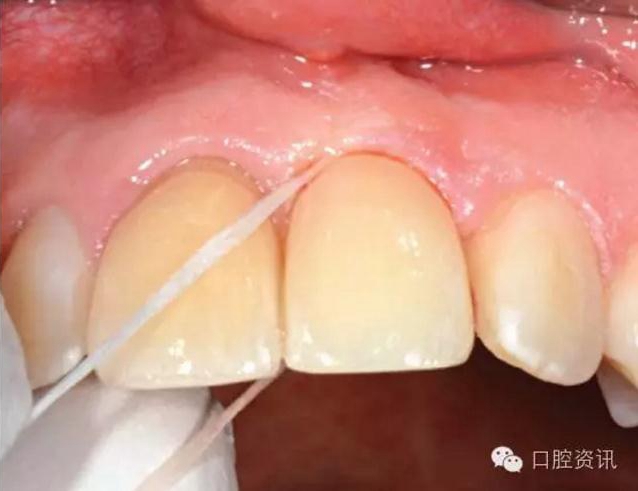

15.jpg

圖15. 使用牙線清潔